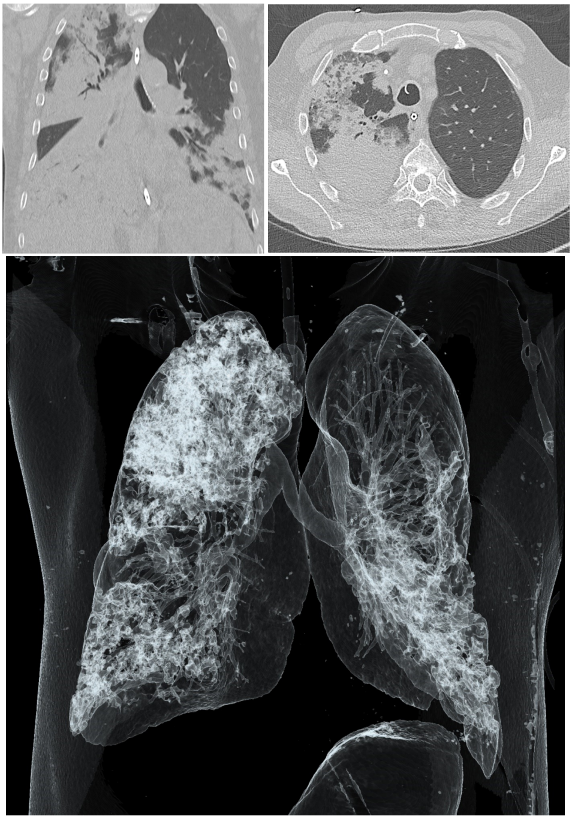

Carbapenem-mediated resistance, particularly in beta-lactamase-producing Pseudomonas aeruginosa strains, represents a global threat within hospital settings [1], [2], [3]. A 61-year-old male patient was admitted to our university hospital with respiratory insufficiency resulting from pneumonia. Initially, he was treated with piperacillin-tazobactam. Axial and coronal non-contrast computed tomography (CT) imaging upon admission revealed multiple infiltrates in the right upper lobe and bilateral lower lobes of the lungs (Figure 1 [Fig. 1]). The patient’s anti-infective therapy was adjusted to meropenem, while benzylpenicillin was concurrently prescribed to treat his streptococcal urinary infection. Due to the rapid onset of acute respiratory distress syndrome (ARDS) and sepsis, extracorporeal membrane oxygenation (ECMO) was initiated in our intensive care unit (ICU). During his hospitalization, a multidrug- and carbapenem-resistant P. aeruginosa strain was isolated from bronchoalveolar lavage (BAL) samples, prompting an escalation of the antimicrobial therapy to cefiderocol (Table 1 [Tab. 1]). Despite intensive clinical treatment, the patient succumbed to his condition four weeks after admission with persistently elevated infection parameters and progressive clinical deterioration, as there were no further treatment options.

Figure 1: CT imaging of patient’s chest at hospital admission. Upper left panel: Axial non-contrast CT image showing infiltrates in the upper and lower lobes of the right lung. Upper right panel: Coronal non-contrast CT image demonstrating infiltrates in the upper right and both lower lobes of the lung. Lower panel: 3D reconstruction of the CT showing the relative sparing of the left upper lobe.